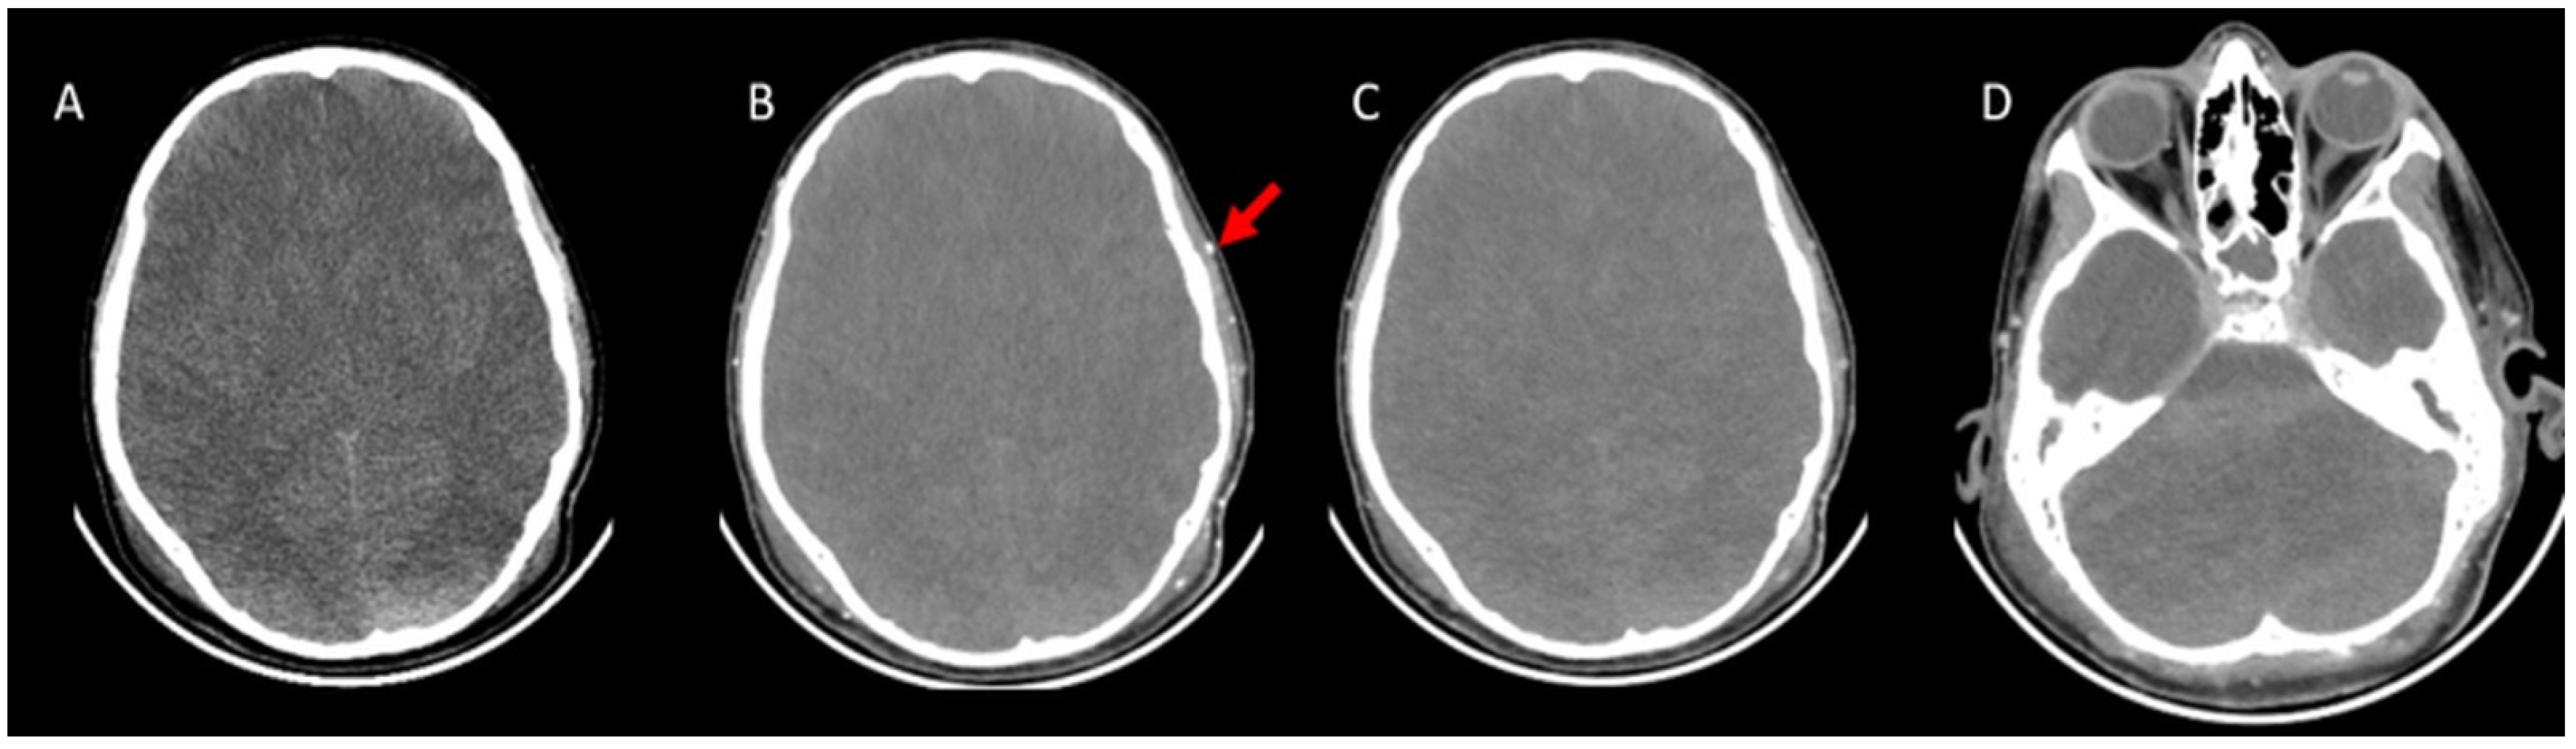

- A60-V60: Absence of opacification in M4 branches of the middle cerebral arteries (MCAs) and ICVs in the venous phase, based on the reference 4-point system by Frampas et al. [11].

- A20-V60: Absence of opacification in M4 branches of the MCAs in the arterial phase and ICVs in the venous phase, based on the revised arteriovenous scoring system by Nunes et al. [12].

- ICV-SPV: Absence of opacification in the ICVs and SPVs in the venous phase, based on the revised venous scoring system by Marchand et al. [10].